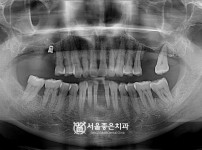

뼈이식 임플란트 5개 - 오스템 임플란트 / 오래전 하셨던 브릿지 2차우식 진행, 발치 후 임플란트

해당 게시물은 의료법 제56조에 의거하여 로그인 후 열람이 가능합니다.

구분 임플란트